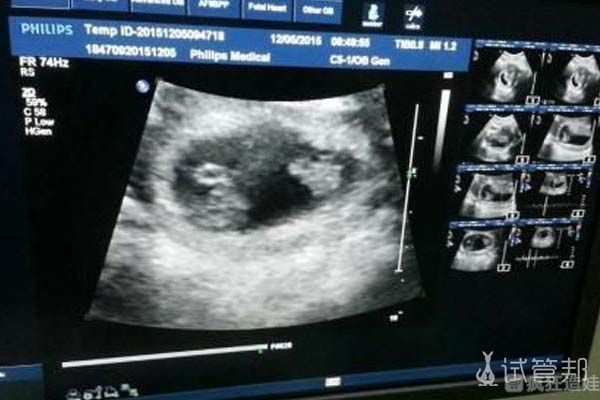

我是选择的重庆附一院进行试管的,当时促排情况不太好,只取出了5个,还进行了二次促排。最后一共有10个可用卵泡,受精成功7个,最后只有2个能用的,也没有什么选择。2个胚胎只有一个达到可胚胎移植标准,所以真的是孤注一掷,幸好宝宝挣气。现在我已经怀孕5个月了,等着鼠宝宝的降生。

我又恢复了3个月,再去医院就诊的时候,医生建议我可以再进行胚胎移植,还有上次剩下的2个胚胎可以用。我就一次性把两个胚胎都胚胎移植了,想着成功率会更高一些。这次心态真的要放松些,可能经历过一次了,也觉得没有这么紧张和害怕了。没想到最后成功了,我听很多在医院认识的姐妹说,她们有的做了3-4次试管才成功的。在医院查到胎心的那一刻,真的是很激动,也希望大家能把这份幸运传递下去。